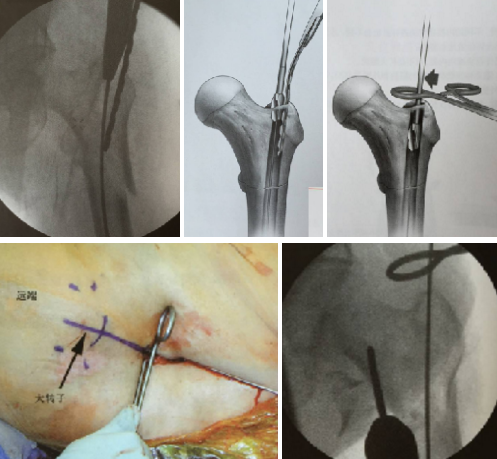

具体操作

首先,我们要在大粗隆近端做一个2~3公分的小切口,建立一个良好的软组织通道。对年龄比较大的、骨质比较疏松的病人,为了减少手术时间,可采用开口器直接开口,直接插钉的方法。开口的同时要特别注意,手指先摸到大转子顶点偏内侧,然后,开口去顺着手指方向插入,开口器一定要紧贴着身体轴线。

开口器顺着髓腔方向旋转地插入,用力的时候因为内侧皮质比较硬,外侧的比较软。所以,开口用力的方向一定是偏内向髓腔方向,大部分情况下都能一次成功。

透视下定位比较准确以后就可以插钉。当然,有的医生经验不是很丰富,手摸心会还不能达到很高的层次。那么,建议还是多透几下,正位、侧位都要多透几下。然后,可以根据髓腔的方向不断地调整,以达到最佳的开口。

也有一些病人骨折线正好位于开口区,或者年纪比较轻,骨头质量比较好,不能通过直接开口的方法插钉,这时候需要克氏针加导针定位的方法,先精确地置入正确位置的导针,然后,再以导针为中心,进一步扩髓以扩大开口。

要特别强调的是,开口一定要充分。否则,很容易造成插钉时骨折的移位。但实际上,由于操作空间的限制以及该处皮质内紧外松的特点,临床上经常会发现扩髓时内侧比较坚硬的皮质,经常会阻挡并且推顶扩髓钻向更松软的大粗隆侧移位,造成进针点外移这种现象。

每个医生都有自己的小窍门来克服这种现象:

- 有的医生可以矫枉过正,开口稍微內移一点

- 有的医生利用手头各种各样的工具,比如说拉钩、剥离子顶着扩髓钻,施加一个向内的分力,以减少外侧皮质的干扰

- 也有的医生用一块小钢板保护外侧壁,以保证其不受干扰

- 或者用导针向上弧形折顶的方法,利用导针本身的弹性以达到对外侧皮质的保护

示意图:开口及扩髓利用器械辅助避免损伤外侧壁